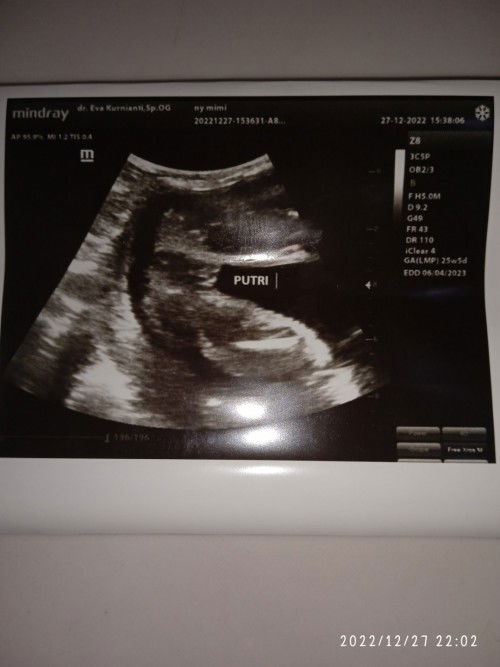

Benargak sih ini bund, jk perempuan??

Hasil USG 25 week

Insyallah kalau dari foto itu cewe bun soalmya aku baby boy jelas banget ada monasnya 😅🥰

kalau cowok begini bun ada Monasnya itu kayaknya itu cewe bun tampak labia mayora nya

cwek bun, kyak hasil usg ku kemarin itu jg seperti itu